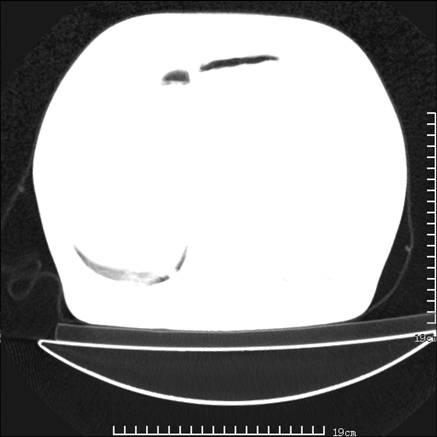

张男,75岁,干咳半年余,小便不利二年,b超检查前列腺增大,未见明显肿块;前列腺癌血生化检查多项指标明显增高。

双肺内多发转移瘤,纵膈淋巴结转移。来源前列腺?建议盆腔mri进一步检查。

双肺转移满了。

两肺广泛转移瘤。